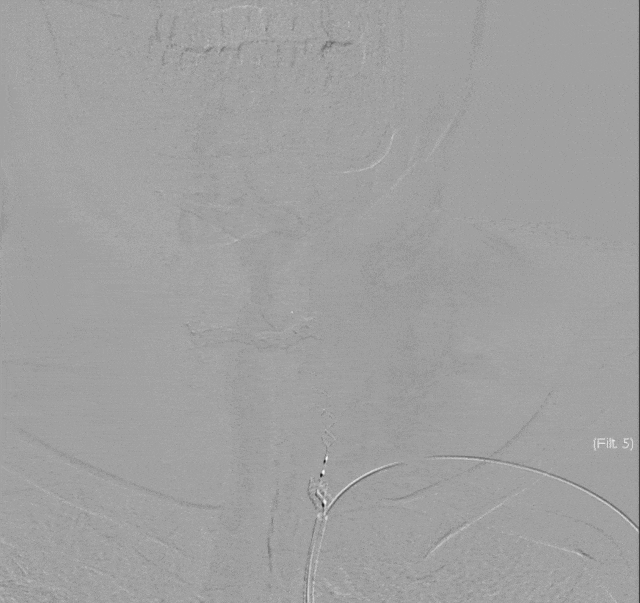

支架植入后造影提示Syphonet®取栓支架内血栓捕获。

利用取栓支架的锚定作用,上高5F 125cm 单弯导管回收Syphonet®取栓支架,检查可见支架体部抓捕到一枚陈旧性暗红色栓子。